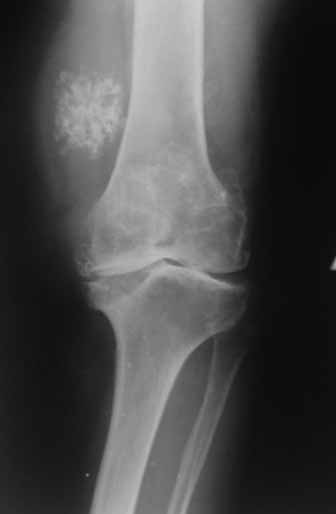

Пациентка 72 лет.Не обследовалась и не лечилась.

Работала поварихой до последнего времени.обратилась за медпомощью впервые.ходит без дополнительной опоры. Основные жалобы на ограничение движений и боли в правом коленном суставе.

Финансовые возможности ограничены.Чем можно помочь? Артродез? Протезирование?

Здравствуйте! А у вас нет ли R-гр? Для установления ст. артроза. Если же пациентка обращается первично, может стоит попробовать консервативное лечение?! НПВП, физиолечение, массаж, внутрисуставные блокады... Артродез и протезирование думаю всегда успеется.

однозначно протезирование

Anatoly Yakushin 08 Апрель 2011, 05:58

Больной несомненно показано эндопротезирование, однако случай не простой. Если у Вас нет достаточного опыта в проведении подобных операций, лучше направить больную в соответствующее лечебное

учреждение. По квоте.